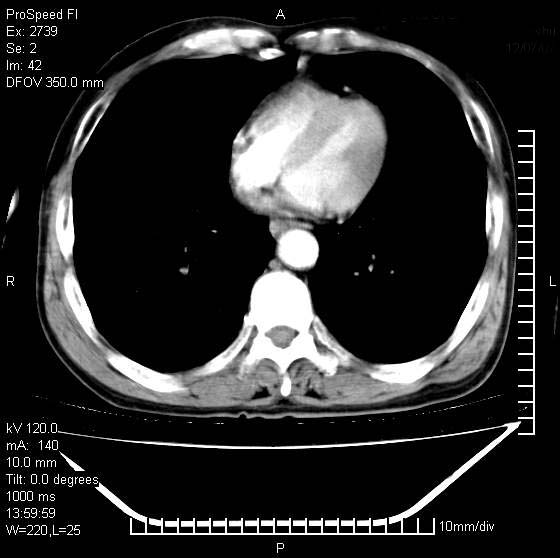

以下是引用andymaomao在2007-12-7 15:54:00的发言:[br]1.双上肺陈旧肺tb灶;[br]2.双中上肺矽肺;[br]3.双肺气肿;[br]4.图中箭头所指乃下腔静脉。

以下是引用山之魂海之韵在2007-12-7 18:59:00的发言:[br]支持矽肺,左肺上叶陈旧性结核,肺气肿。箭头所指乃下腔静脉。下腔静脉显影比主动脉显影迟,增强动脉后迟可以是不均匀的。

以下是引用chengjiaqiu1在2007-12-7 17:49:00的发言:[br]矽肺,左肺上叶陈旧性结核,肺气肿。中箭头所指乃下腔静脉。